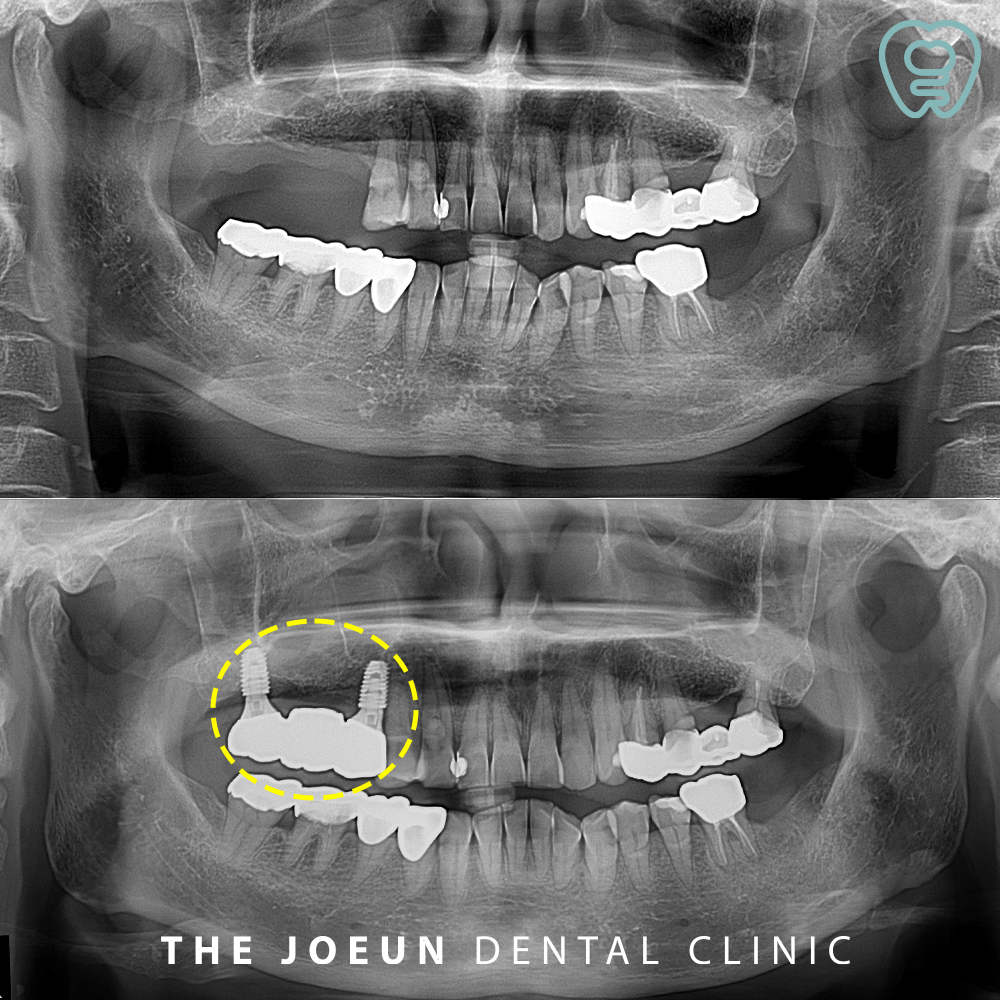

오늘은 발치 후 즉시 임플란트 식립과 상악동 거상술을 함께 진행하여 4개월에 완성하신 환자분을 소개해 드리려고 합니다.

환자분께서는 오른쪽 위 어금니를 타 치과에서 발치하시고 임플란트를 진행하고 싶으시다며 내원해 주셨는데요. 발치를 하신 지 시간이 꽤 지났다고 말씀해주셨지만 기존의 잇몸 염증으로 인해 잇몸뼈가 임플란트 식립을 하기에는 부족하였고, 상악동이 아래로 내려와 있어 상악동 거상술을 동반한 임플란트 식립 계획을 수립하게 되었습니다.

당일 바로 상악동 거상술과 임플란트 식립을 진행하였는데요. 치조정 접근을 통한 상악동 거상술을 함께 진행하였습니다.

식립 약 4개월 뒤 최종 보철물까지 완료하였습니다.